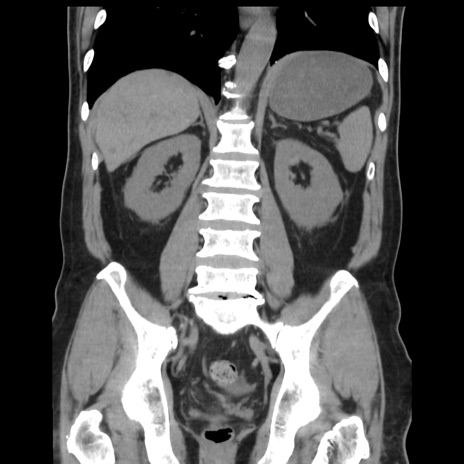

症例16(冠状断像)

【症例】 70歳代男性

【主訴】 腹痛、嘔吐

【現病歴】 約1ヶ月前より間欠的に腹痛と嘔吐あり、当院消化器内科を受診したところCTで多発する肝臓のLDAを指摘され、精査中であった。以降は消化器症状は安定していたが、2日前より嘔気と腹痛があり、同日より排便・排ガスが消失した。改善認めず、 本日、救急外来を受診した。

【身体所見】意識清明・会話良好、BT 36.3℃、BP 127/80mmHg、 P 80bpm、腹部:膨満あり、平坦・軟、上腹部正中および下腹部正中に圧痛あり、反跳痛なし、筋性防御なし。

【データ】WBC 7200、CRP 0.77